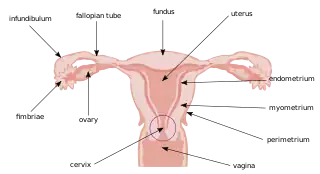

Uterus and uterine tubes (myometrium labeled at center right) | |

The myometrium is the middle layer of the uterine wall, consisting mainly of uterine smooth muscle cells (also called uterine myocytes[1]) but also of supporting stromal and vascular tissue.[2] Its main function is to induce uterine contractions.

The myometrium is located between the endometrium (the inner layer of the uterine wall) and the serosa or perimetrium (the outer uterine layer).